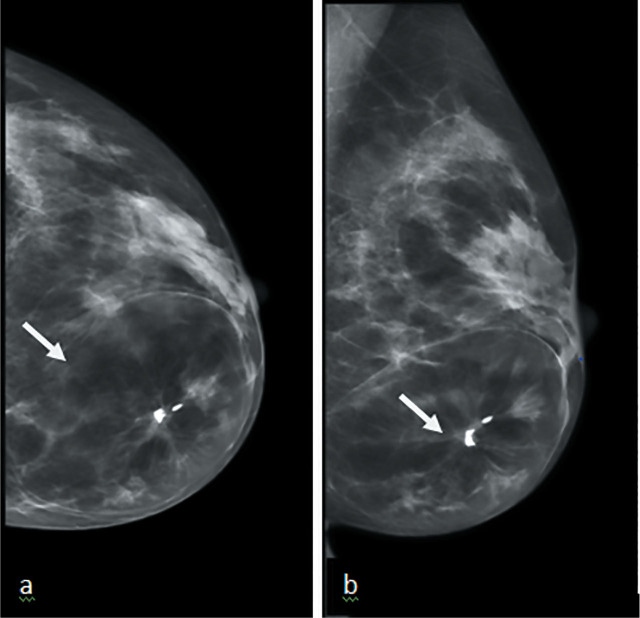

Case description: We present two cases of breast hamartoma in 51 and 61 years old female who presented to us through screening and symptomatic clinics.Both cases had imaging findings typical for diagnosis of hamartoma however there was a distortion within the hamartoma which raised possibility of malignancy and prompted a core biopsy and MDT discussion.

Practical implication: Many hamartomas have typical benign imaging appearances and require no further investigation. Biopsy is needed in atypical looking hamartomas to exclude a breast carcinoma, which although rare may develop within a hamartoma. Multidisciplinary team discussion is crucial in the management of atypical cases to ensure radiological-pathological concordance.